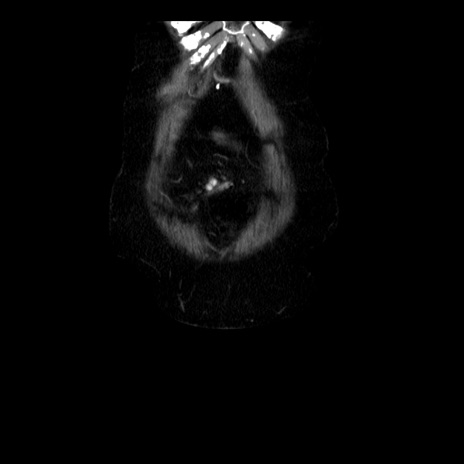

横断像